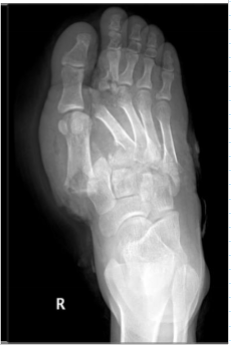

radiology - gout

most often affects the metatarsal-phalangeal joint of the great toe with the juxta-articular erosions and/or little to no osteoporosis

tophi = late manifestations of the disease